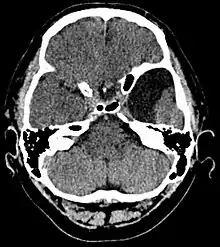

![]() | |

| An MRI of a 25-year-old woman with left frontotemporal arachnoid cyst. | |